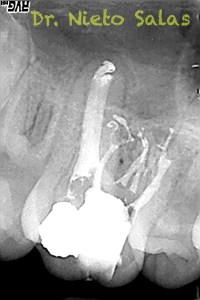

No es habitual en nuestra práctica casos como estos, pero os pongo algunos más:

Una vez desobturados los conductos, empezamos a hacer una endodoncia convencional.

A este caso le tengo especial cariño por ser el primero que hice;